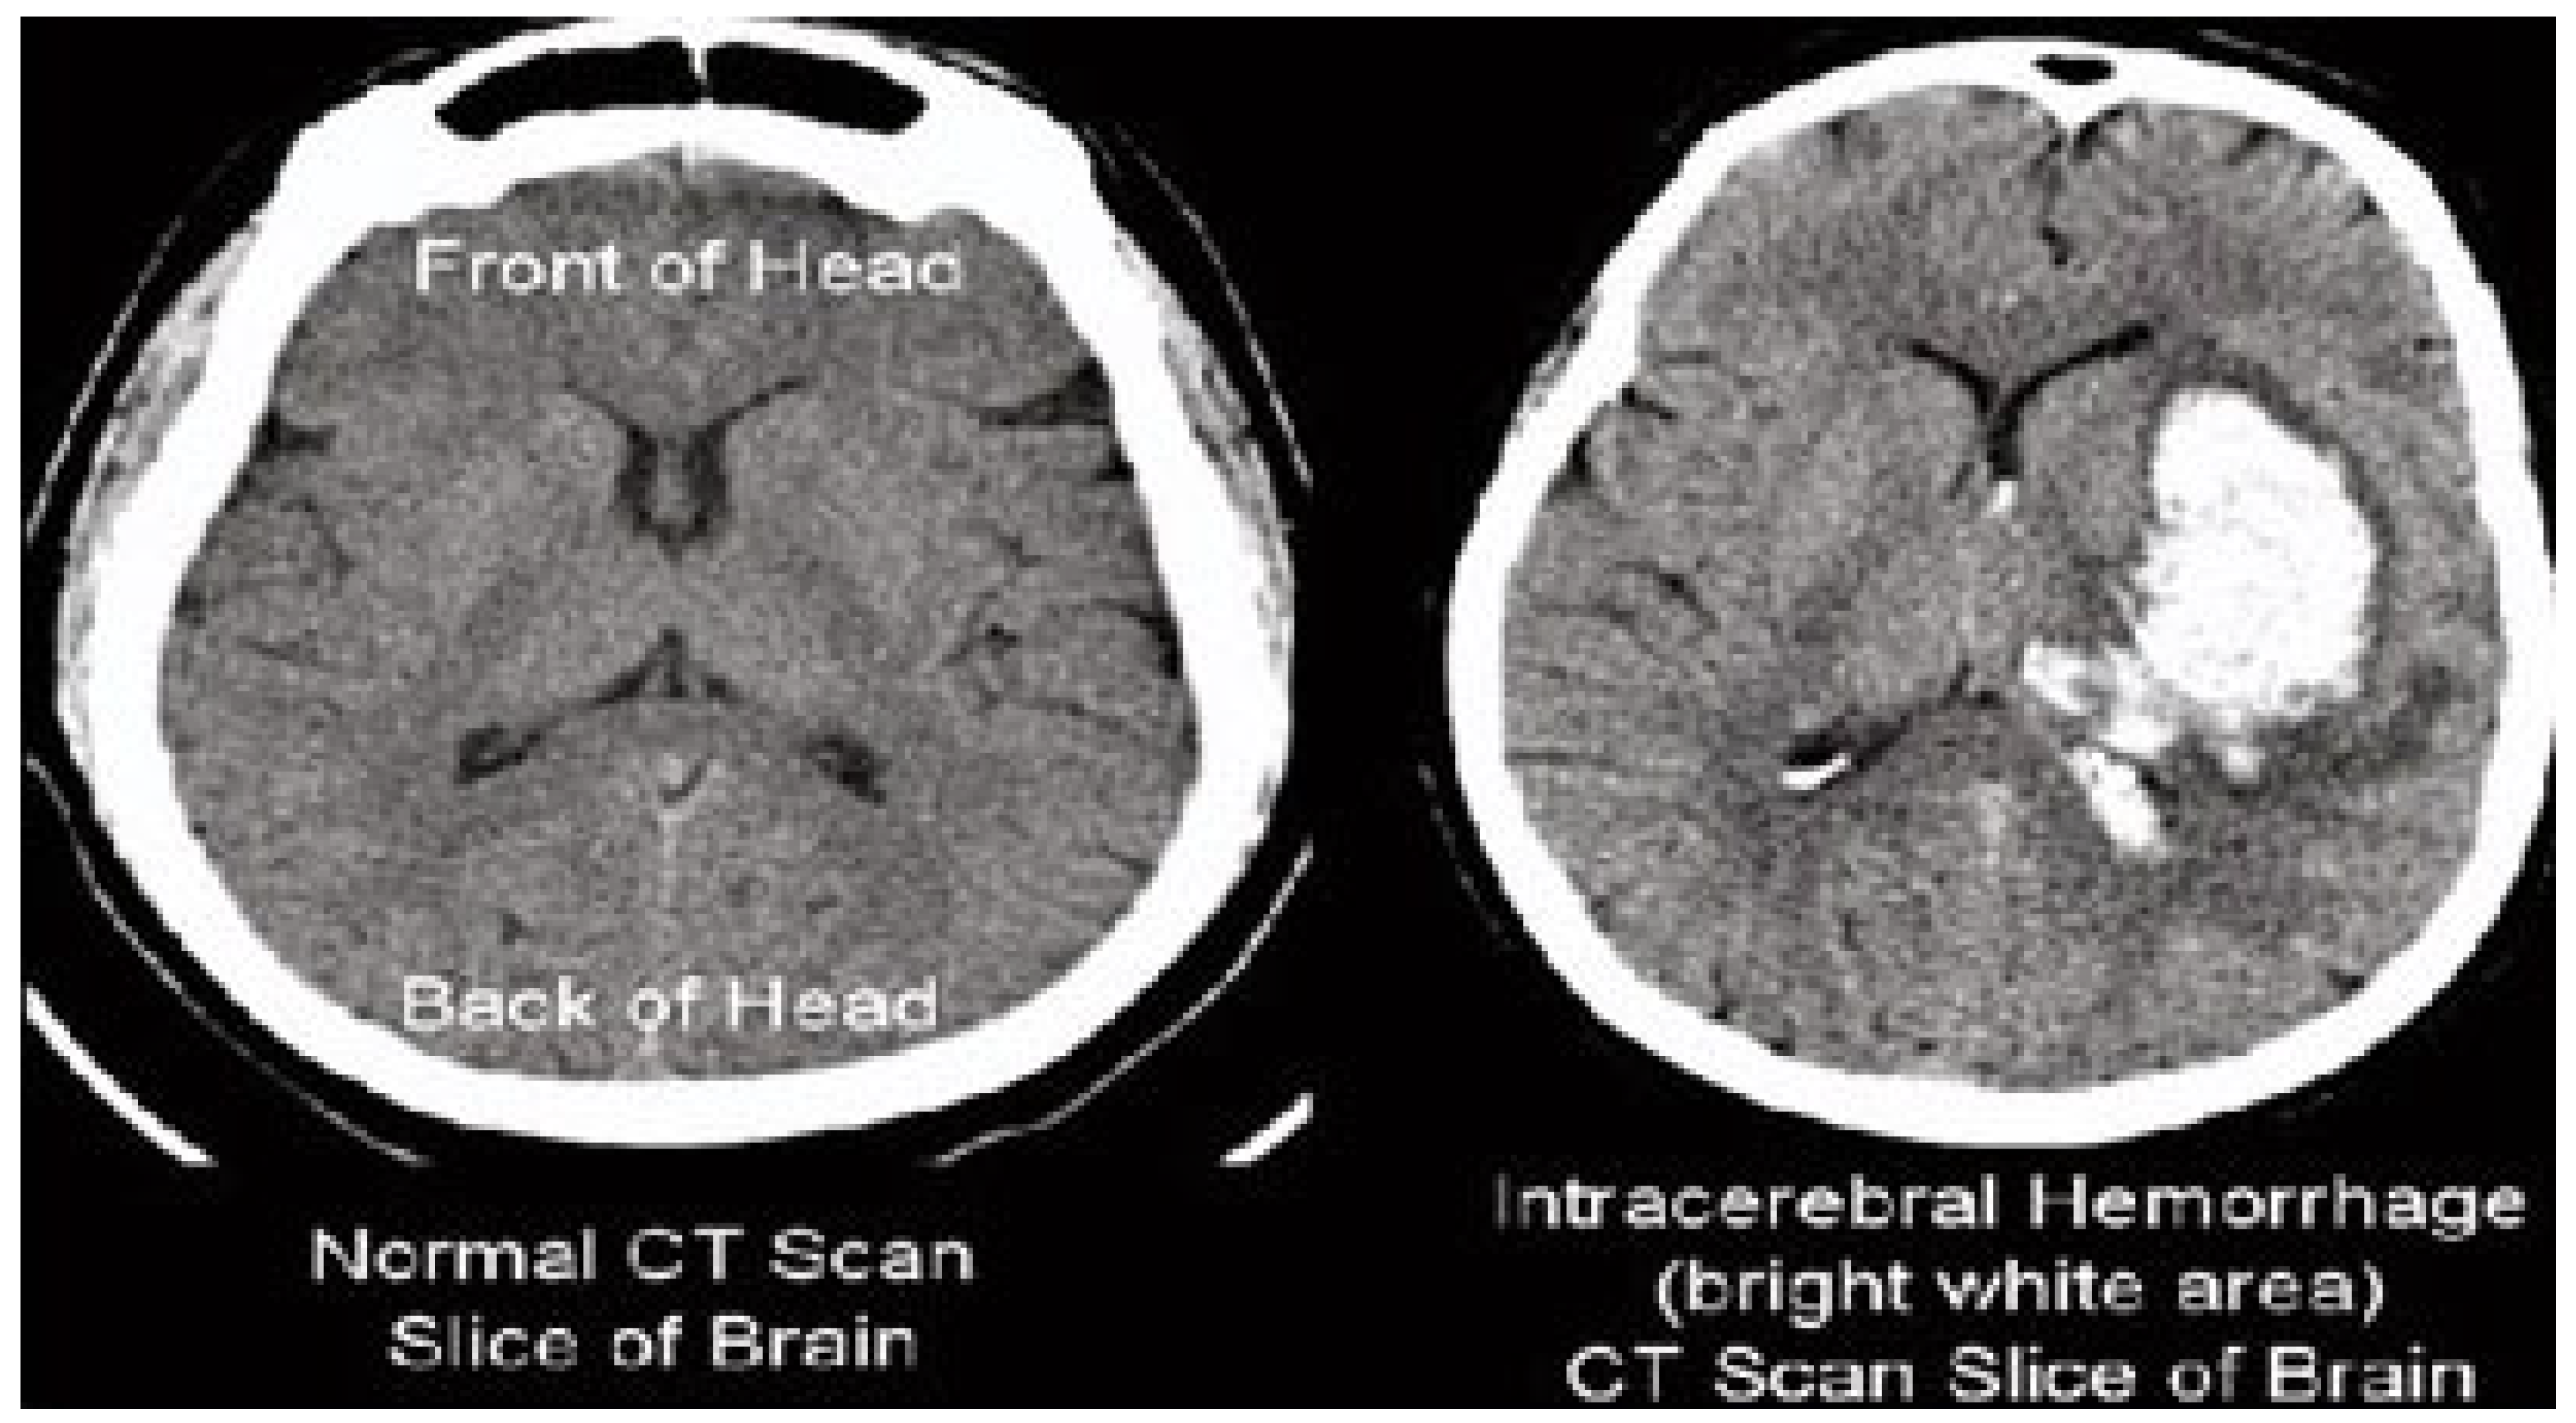

The results of the steganography technique are shown in Figure 2; the changes in both the cover image and the steganography image cannot be distinguished. This demonstrates the superiority of the LSB replacement method in the field of steganography. The resulting steganography image is then transformed to render the image unreadable, and compression techniques are used to store the medical image in a database properly. This scenario is illustrated in Figure 3. This diagram shows the order of conversion, compression, decompression, and inverse conversion processes. To realize this methodology, we took as input cerebral hemorrhage steganography images already embedded in patient data and applied the DWT to obtain the transformed images.

Figure 2.

The embedded image.

The “dwt2” method is used for the conversion. In the DWT process, the original image is decomposed into up to two levels using the “Haar” wavelet. This decomposition produces horizontal, vertical, diagonal, and proximity components. The decomposed components are reconstructed using the DIWT to recover the original image. This strategy is illustrated in Figure 2, and the compression method takes a decomposed image as input and compresses it using a wavelet packet compression technique using “Haar” wavelet packets. The compression method, “wpdencmp,” uses a soft thresholding technique that uses wavelet packets to compress the image and compute the threshold. This compression concept is illustrated in Figure 3, along with histograms of the original and compressed images. A step-by-step compaction process is shown in Figure 4. At each level, the images are refined, and the differences between levels are visible. The higher the number of coding levels of compression, the higher the image’s compression ratio and recovered energy. The compressed image is decompressed by wavelet packet reconstruction using the accounting matrix values of the decomposed image. Horizontal, vertical, diagonal, and proximity components are extracted from the decompressed image, and an IDWT is applied to recover the original image. A title image embedded in the patient data is visualized.

In Figure 3, the steganography image of the brain hemorrhage is taken, and DWT is applied. After compression, the compressed image is displayed as a bar graph. The wavelet reconstruction method recovers the compressed image from the compressed image. The target image is retrieved from the decompressed image by applying the IDWT method to the previous step. Figure 4 represents the DWT and IDWT of the brain hemorrhage image. A sample segmentation of the transformed image is also displayed.